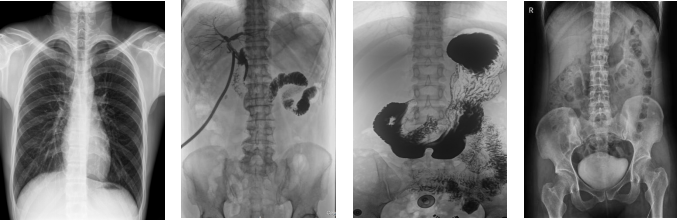

PLD8000C數字胃腸DR機全面突破傳統X射線攝影透視理念,成像部件采用新型動態平板探測器,輕松解決數字攝影、數字透視、數字造影等功能,并使數字透視獲得超大尺寸和清晰的圖像效果。滿足放射科、體檢中心、影像中心、內科、婦科、外科、急診科、骨科、創傷科、消化科等科室的各種臨床檢查需求。如果您想采購這款數字胃腸DR機,歡迎咨詢400-025-6366。